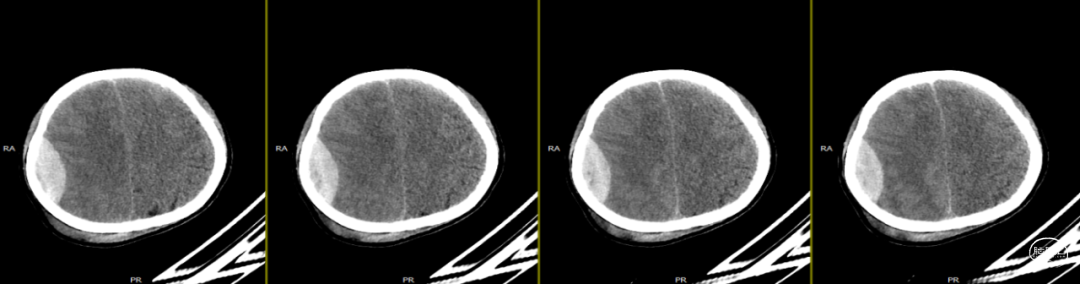

第2次手术后第17天,行颅脑CT检查(如上图),科室讨论仍建议去骨瓣清创,但患者情绪波动明显,拒绝去骨瓣;经协商后行硬膜外脓肿置管引流术。术中根据术前规划,切开颞顶部部分头皮,高速磨钻经骨缘与骨瓣之间磨出骨孔及骨槽,可见骨缘硬脑膜增生,深部硬膜增厚,并伴有灰黄色粘稠脓性液体流出,无明显异味,使用无菌注射器收集脓液约7ml,备细菌培养等检查;置引流管于硬膜外,骨瓣下,反复使用温生理盐水冲洗至水清晰,接负压吸引,及引流袋;术后继续使用万古霉素及美罗培南联合抗炎治疗。术后每日使用万古霉素溶液冲洗硬膜外腔1次。

第3次术后第9天复查颅脑CT(如上图)。

第3次术后16天,复查颅脑MRI(如上图),硬膜外及皮下异常信号较前明显减少,负压引流管引流不明显,拔除负压引流管,继续使用头孢曲松+多西环素口服联合抗炎治疗。

第3次术后23天,拔管后7天复查颅脑(如上图)。

第3次手术后49天,出院后2周复查颅脑CT情况(如上图),刀口愈合正常,患者回归日常生活、学习。